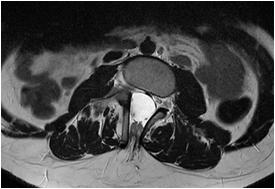

Fig 1 — CT Imaging from a patient of Basal Ganglia hemorrhage in the present study

(5) The individual regions we had observed to cause swallowing disturbance are as follows : Infarcts :

•MCA territory infarcts & PCA territory infarcts (especially of P1 and P2 region ) caused Swallowing Dysfunction.Similar findings were observed by Paciaroni M, et al17 and Javed K, et al36 respectively.

•Pontine infarct & Lateral Medullary Infarct depending on the size and subsite involved caused Swallowing Dysfunction. Similar findings were observed by Chang MC, et al21 and Ayodogdu, et al19 respectively.

Hemorrhage :